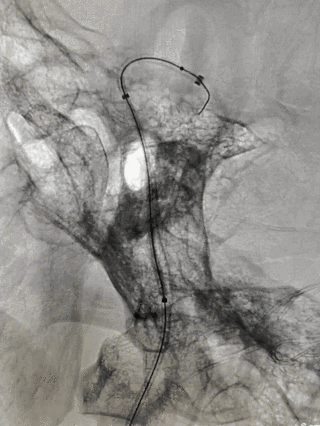

图4

由于颈部血管迂曲明显,选择Neuron MAX 6F 088长鞘顺利到达右颈内动脉C1末端做近端支撑。Synchro 0.014 200微导丝及XT-27微导管引导CAT 5(Catalyst 5)导管同轴越过右颈内动脉末端动脉瘤至右大脑中动脉瘤M1末端后撤出微导丝微导管,保留CAT 5导管。

选取Surpass Streamline 5mm╳40mm经CAT 5导管释放。由于血管迂曲,支架与CAT 5导管摩擦较大,Surpass Streamline无法推出。

图5

将Neuron MAX 6F 088长鞘尽可能送达右颈内动脉岩骨段,将Surpass Streamline在体外推送至支架导管头端MARK点,再经CAT 5导管释放。考虑动脉瘤颈宽大,载瘤动脉瘤样改变,Surpass Streamline远端定位右侧大脑中动脉M1中远段,结合推拉技术,顺利释放Surpass Streamline,并行导丝充分按摩。

图6